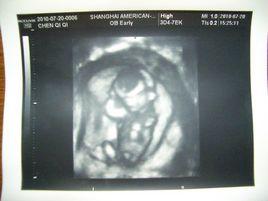

頂臀徑:又稱 頭臀長(crown-rump length 簡寫 CRL),指胎兒從顱頂頂部到臀部外緣的距離,一般懷孕7-12周左右測量。

超聲檢查早孕胎兒時,常用頂臀徑估測胎兒的孕齡,此為最為準確的估測方法。6周初由於胚芽太小,測量不準確,隨著孕周的增大,胚胎的生長,其形態曲線為C形,頭端相對較大而容易辨認。故此採用以下公式計算妊娠齡。

公式: 妊娠齡(周)=CRL(cm)+6.5

測量標準切面:取胎體或軀幹最長,最直的正中矢狀面切面圖像。

(1)適用於孕7-12周。

(2)要測量胎兒的最長徑線(測量三次取均值)。

(3)測量時不包括胎兒的肢體及卵黃囊。